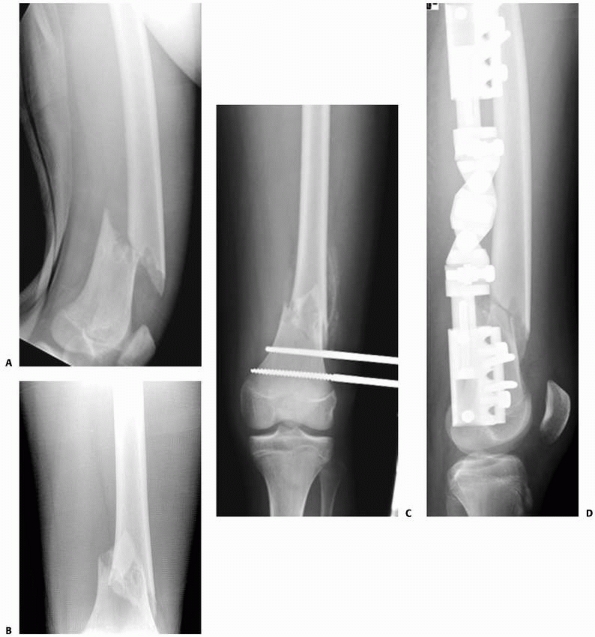

![]() |

FIGURE 22-2 A. Femoral fracture through a poorly demarcated mixed, osteoblastic, osteolytic lesion—an osteosarcoma. B. Sclerotic borders of this lesion in the distal femur are typical of a pathologic fracture through a nonossifying fibroma.

nonossifying fibroma (Fig. 22-2).